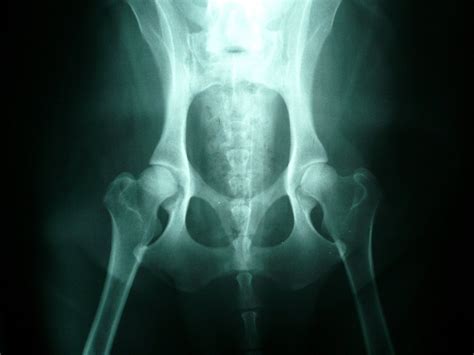

Jedno z najčastejších ortopedických ochorení u veľkých a obrých psích plemien je dysplázia bedrového kĺbu. Ide o dedičnú vývojovú vadu, pri ktorej bedrový kĺb nezapadá správne do jamky. Mnohým z týchto stavov sa môžete aspoň čiastočne vyhnúť vďaka správnej starostlivosti o šteniatko a rastúceho psíka. Vtedy totiž môžete ovplyvniť jeho stravovacie návyky a výživu.

Dysplázia bedrového kĺbu (DBK) je dedičné ochorenie pohybového aparátu u psov, pri ktorej hlavica stehennej kosti správne nezapadá do panvovej jamky, pretože kĺb sa nevyvíja tak, ako by mal. Toto nesprávne zarovnanie môže viesť k čiastočnej alebo úplnej dislokácii a časom vedie k opotrebovaniu chrupavky, zápalu a ťažkej artritíde.

Diagnostika sa stanovuje na základe klinického vyšetrenia a röntgenu, ktorý odhalí rozsah poškodenia kĺbu. Ochorenie sa dá zdiagnostikovať a určiť stupeň dysplázie jedine RTG vyšetrením vykonanom v celkovej anestézii na oficiálne schválenom RTG pracovisku.

Pri výbere chovných zvierat sú potrebné určité kritériá na vyhotovenie röntgenových snímok a ich hodnotenie. U niektorých plemien, v niektorých krajinách alebo pri odborných posudkoch, je potrebný ďalší röntgen s roztiahnutými stehnami a nadvihnutými členkami (tzv. „žabí snímok“), pretože zmeny okraja kĺbovej jamky a stehenných kostí sú tak lepšie viditeľné.